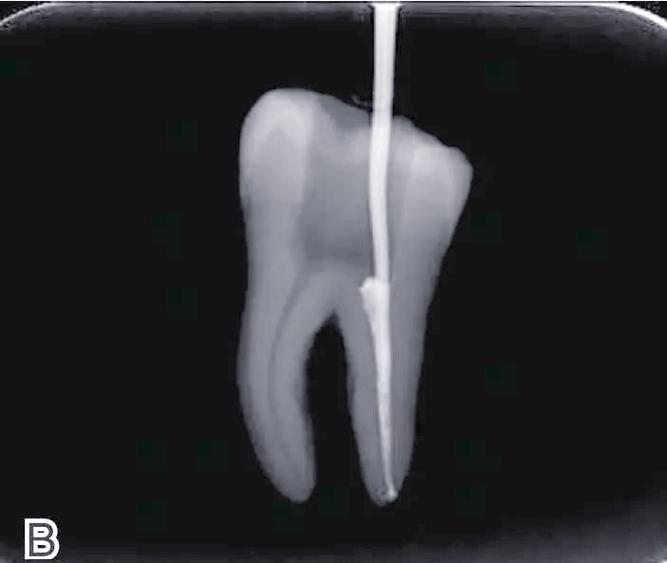

试尖是确定主牙胶尖尺寸的关键步骤,选择与主锉锥度匹配的主牙胶尖(通常为主锉的锥度,如#25主锉选#25牙胶尖),在牙胶尖上标记工作长度,插入根管内试插,理想的主尖应尖端刚好到达根尖狭窄区,有轻微摩擦感(回拉1-2mm有阻力),且根管内剩余空间为副尖填塞留出余地(一般为主尖直径的1/4-1/3),若主尖过松(无摩擦感)或过紧(无法就位),需更换不同尺寸的牙胶尖重新试尖。

去除根管口多余的牙胶尖(可用加热器或挖器烫除),检查充填体表面光滑、无气泡,随后拍摄X线片确认充填效果:理想状态为“恰填”——牙胶尖尖端达工作长度,封闭剂均匀分布于根管壁,无超填(超出根尖孔)或欠填(未达工作长度)。

| 充填完成检查 | 去除多余牙胶,拍摄X线片确认恰填 | X线片需显示封闭剂均匀分布,无超填或欠填 |